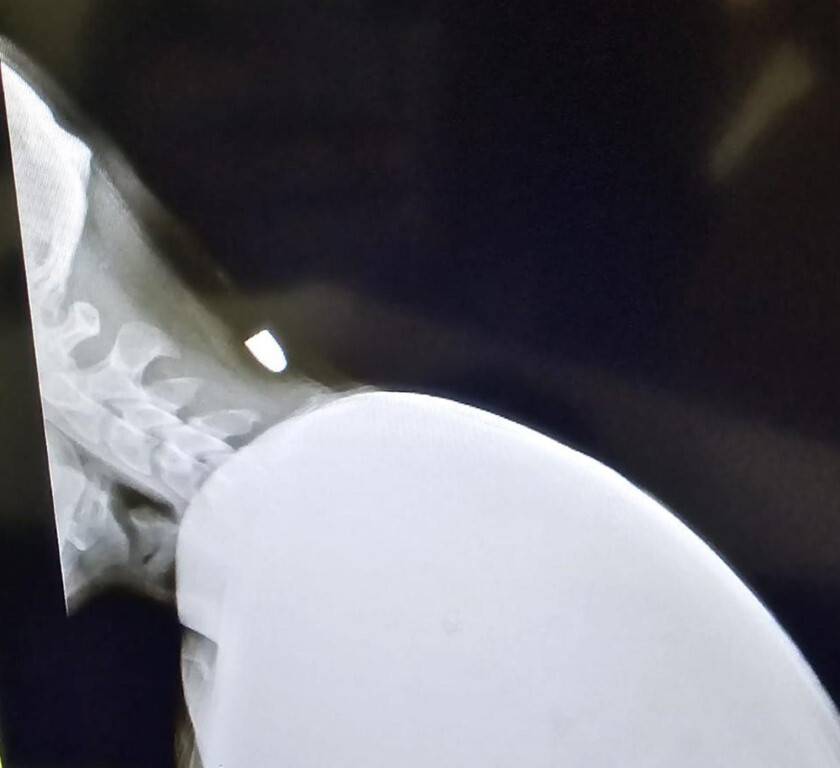

Kırıkhan'da, Mimar Sinan Mahallesi’nde çalıştığı iş yerinde mola verip arkadaşlarıyla sohbet ederken eğilen Yavuz’un ensesine nereden geldiği bilinmeyen bir mermi isabet etti. O an ensesinde ani bir ağrı hisseden Yavuz yere yığıldı ve arkadaşları tarafından hızla hastaneye götürüldü. Hastanede yapılan tetkikler sonucunda ensesine bir mermi isabet ettiği tespit edildi. Geçtiğimiz pazartesi günü 40 dakika süren bir ameliyatla ensesindeki mermi çıkarılan Yavuz, taburcu edilirken sağlık durumu günden güne iyiye gidiyor. Olayla ilgili olarak polis ekipleri de inceleme başlattı.

Arkadaşlarıyla birlikte oturduğu sırada yorgun merminin isabet ettiğini anlatan Yunus Emre Yavuz, "Akşam saat 19.30 civarında mola vermiştik ve otururken biraz eğildim. Eğildiğim an mermi düştü, biri sanki kafama sertçe sopayla vurmuş gibi hissettim. Arkadaşlarım yaraya bakınca mermi olduğunu fark etti. Hastaneye gittik ve röntgenle ensede mermi olduğu anlaşıldı. Pazartesi günü ameliyat oldum; 40 dakika sürdü ve şükürler olsun sağ salim çıktım. Kurşun, incelenmek üzere Adana'ya gönderildi. Zorlu bir süreçti ama atlattım," dedi.